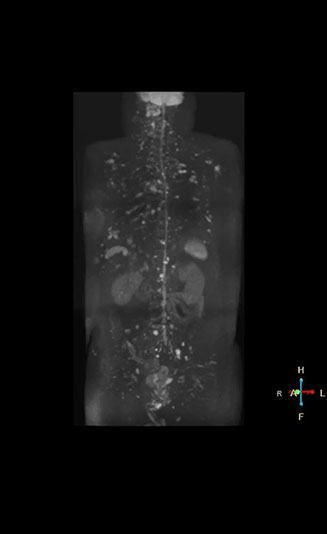

High contrast between lesions and background is beneficial in oncology patients

Radiologist Hiroshi Nobusawa, MD, PhD, explains that the coronal DWIBS protocol for whole body DWI is excellent for visualizing lesions in oncology patients. “About 90% of the DWIBS exams are done in this type of patients. The remainder of DWIBS exams are performed to gain information in cases of fevers of unknown origin,” he says.

“The DWIBS sequence’s value in oncology cases is due to the high contrast it creates between lesions and surrounding tissue. Whole body DWI is requested by physicians who need to clarify TNM staging or determine therapeutic strategies, oncologists in need of diagnosis or follow-up scans, surgeons who need to see the presence of distant lesions that are sometimes difficult to detect by CT before surgery, and urologists for the evaluation of bone lesions, and the effect of chemotherapy and radiotherapy.”

Dr. Nobusawa notes that acceptance of whole body DWI accelerated after the hospital installed the Ingenia 1.5T which allowed them to optimize the protocol to their needs. “The Philips system helped us promote the technique, because the DWIBS image quality was so high with Ingenia. It provides high quality in the coronal images, and a short acquisition time plus high SNR thanks to the dStream technology,” he says.

In certain cases, radiologists now choose DWIBS to make diagnoses that used to depend on nuclear medicine studies. “We don’t have SPECT or PET in our hospital, so for instance for visualizing metastasis and monitoring the effect of treatments such as chemotherapy or radiotherapy, we used to refer patients outside the hospital. Now, these patients are sent to MRI for our whole body protocol with DWIBS,” Mr. Naka says.

“Our radiologists are confident when using our current exam with DWIBS and appreciate that it provides more information than nuclear medicine. The number of referrals is increasing, including referrals from other hospitals that cannot provide DWIBS. And because the scan time is short, we immediately choose DWIBS when oncology patients are referred.”

Finally Dr. Nobusawa concludes, “As soon as you understand the usefulness of DWIBS exams with the Ingenia system, surely you would like to use it. It is also beneficial for patients because DWIBS does not involve radiation exposure as in PET or SPECT. We hope that DWIBS once will be adopted as a gold standard in the care for oncology patients.”